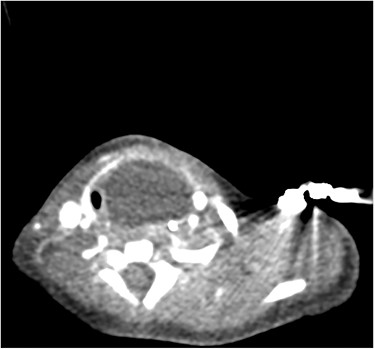

Sagittal barium sallow illustrating the presence of an oesophageal diverticulum, filled with contrast on swallowing.

At age 8 months, the patient was admitted to hospital from clinic due to worsening stridor. She underwent a further MLB that once again illustrated a cyst. An ultrasound scan was performed intraoperatively to aid with emptying of the cyst, and an incidental finding of a connection between the cyst and the cricopharyngeal region was identified, in keeping with a diagnosis of an oesophageal diverticulum. This was later confirmed on a barium swallow study (Fig. 4). Following the MLB, the patient remained clinically stable; the stridor resolved.